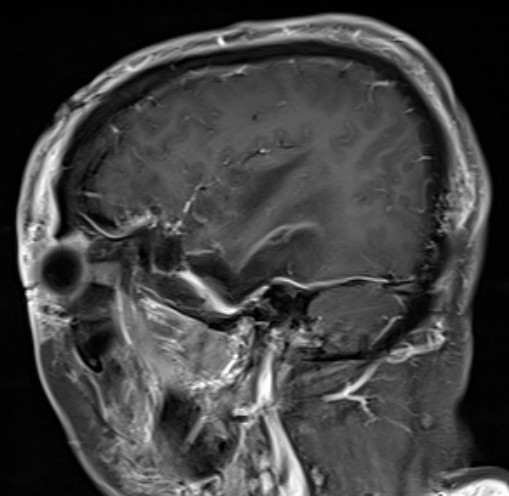

右侧扩大翼点开颅,显微镜下切除肿瘤

术后复查肿瘤近全切除